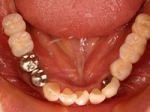

両側5歯症例 主訴-義歯のバネが壊れて手前の歯が痛んできた。 術前(旧義歯装着、鏡像)

術前(下顎粘膜面、鏡像)